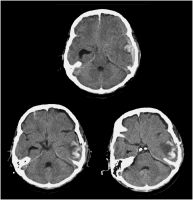

Kontusionsblutung

Abbildung 2: Patient mit Zunahme der Kontusionsblutungen 24 Stunden nach Operation des Epiduralhämatoms